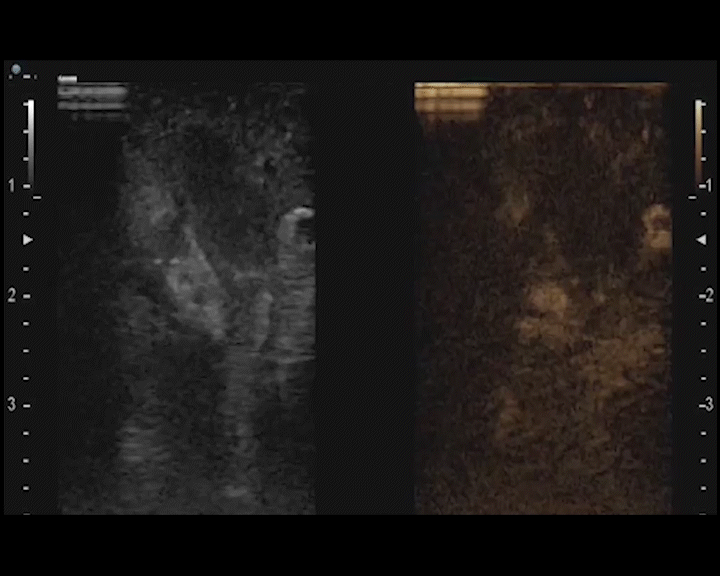

Angiogenesis and vasculogenesis can be a prognostic indicator as prostate cancer evolves. The detailed assessment of this kind of subtle tumour microvascularity can enable better localisation, characterisation and guidance of biopsy or treatment. Which is why our contrast-enhanced ultrasound feature provides vascular information beyond Doppler possibilities, with wideband pulse inversion and tissue reduction techniques – so you can look as closely as possible.

Our contrast-enhanced ultrasound delivers vascular information beyond Doppler possibilities. You can view wash-in and wash-out times for circulatory information on the renal parenchyma and focal lesions. You can characterise hypovascular or atypical tumours; solid or cystic masses; pseudotumours; ischaemia; or infections. You can also use it for precise needle guidance during biopsies, radiofrequency, cryo or microwave ablations.

With our contrast-enhanced ultrasound you can understand vascularisation beyond Doppler possibilities – for example when imaging hypovascular or avascular lesions. It helps you assess more confidently - from testicular segmental infarctions, to the extent of viable tissue after trauma, to the feeding artery. Which means you’re quipped with more information to make improved clinical decisions.